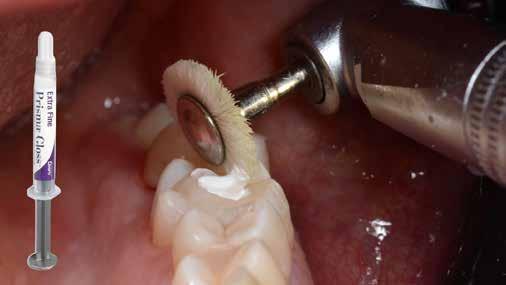

végső polírozása

A végső polírozás célja egy sima, „zománcszerű” felszín kialakítása, amely a páciens lágyrészei számára komfortos, esztétikailag kedvező, valamint ellenáll a lerakódásoknak és az elszíneződésnek. Ez a folyamat négy fázisból áll.

1. fázis

Finom és szuperfinom, közepes méretű polírozó korongok alkalmazásával 10 000–15 000 fordulat/perc sebességen történik a restauráció peremének polírozása. A korongokat hátrafelé irányuló mozdulatokkal, 45°-os szögben kell vezetni a fog hossztengelyéhez képest.

(Fontos: ne váltsunk szuperfinom korongra addig, amíg a finom koronggal el nem távolítottunk minden látható karcolást a tömés felszínéről!)

2. fázis

Finom, gyémánttal impregnált szilikon polírozófejet használunk vízhűtéssel a restaurátum széleinek és a csücsök-lejtők polírozására. Ez a lépés fokozza a restauráció fényét, a karcolások már a durva finírozási szakaszban el lettek távolítva.

3. fázis

Kecskeszőr kefét (pl. Shiny S, https://optident. co.uk/product/shiny-s-goat-hair-brushes/) célszerű alkalmazni stabil nyomással, vízhűtés nélkül, a restaurátum barázdarendszerének polírozására. A polírkefe pumisz pasztával (pl. Vertex® Pumice Plus, https://www.dentaltotal.es/images/ marcas-dentaltotal/VERTEX/CATALOGO_VERTEX.pdf) használandó. Ez a lépés kiküszöböli a barázdákban maradó karcolásokat, amelyek középtávon hajlamosak elszíneződni.

4. fázis

A végső fényesség az 1 mikron szemcseméretű, alumínium-oxid alapú, vízbázisú polírozópasztával (pl. Enamelize®, Cosmedent; https://www.cosmedent.com/product-category/finishing-and-polishing/) érhető el, valamint filc polírozófejek és korongok segítségével. A polírozás fokozatosan

növekvő fordulatszámmal (3000–20 000 fordulat/perc) és csökkenő nyomással történik. A pasztát mindig a fogra/restaurációra kell felvinni, nem pedig a korongra, így elkerülhető a paszta szétszóródása a kezelőben. (Lásd a 10. és 11. ábrát.)

Ezt követően a fogat puszter használatával letisztítjuk, majd a pácienst elbocsátjuk.